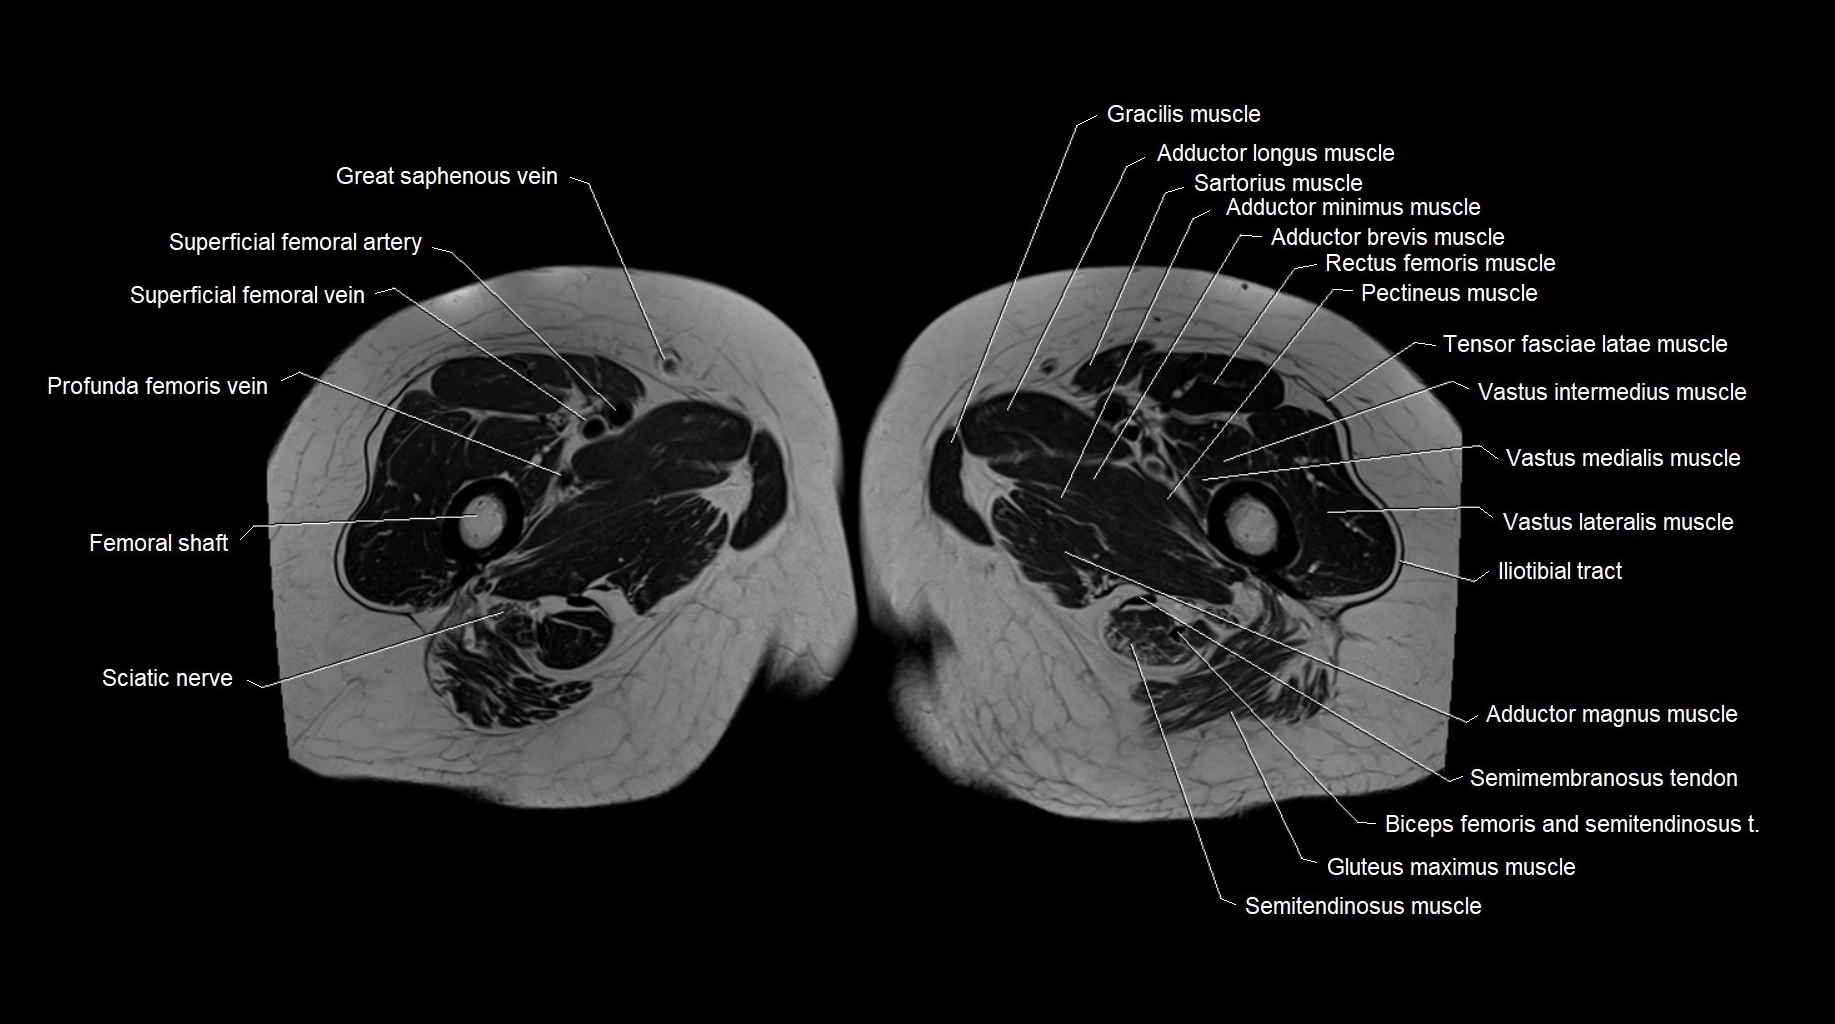

MRI images